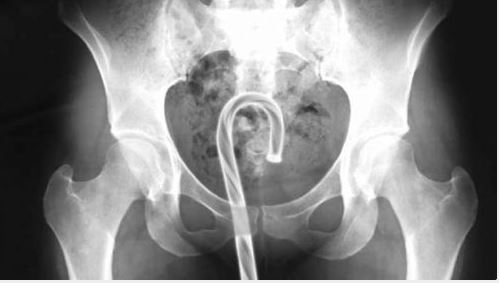

Doktorların görüp yok artık bu nasıl mümkün olur dedikleri röntgen filmleri..

Doktorluğun zor bir meslek olduğu malum. Üstelik bu mesleğin icra ederken bazı zamanlar öyle vakalar ortaya çıkmış ki, doktorlar bile anlamlandırmakta zorluk çekmişler.